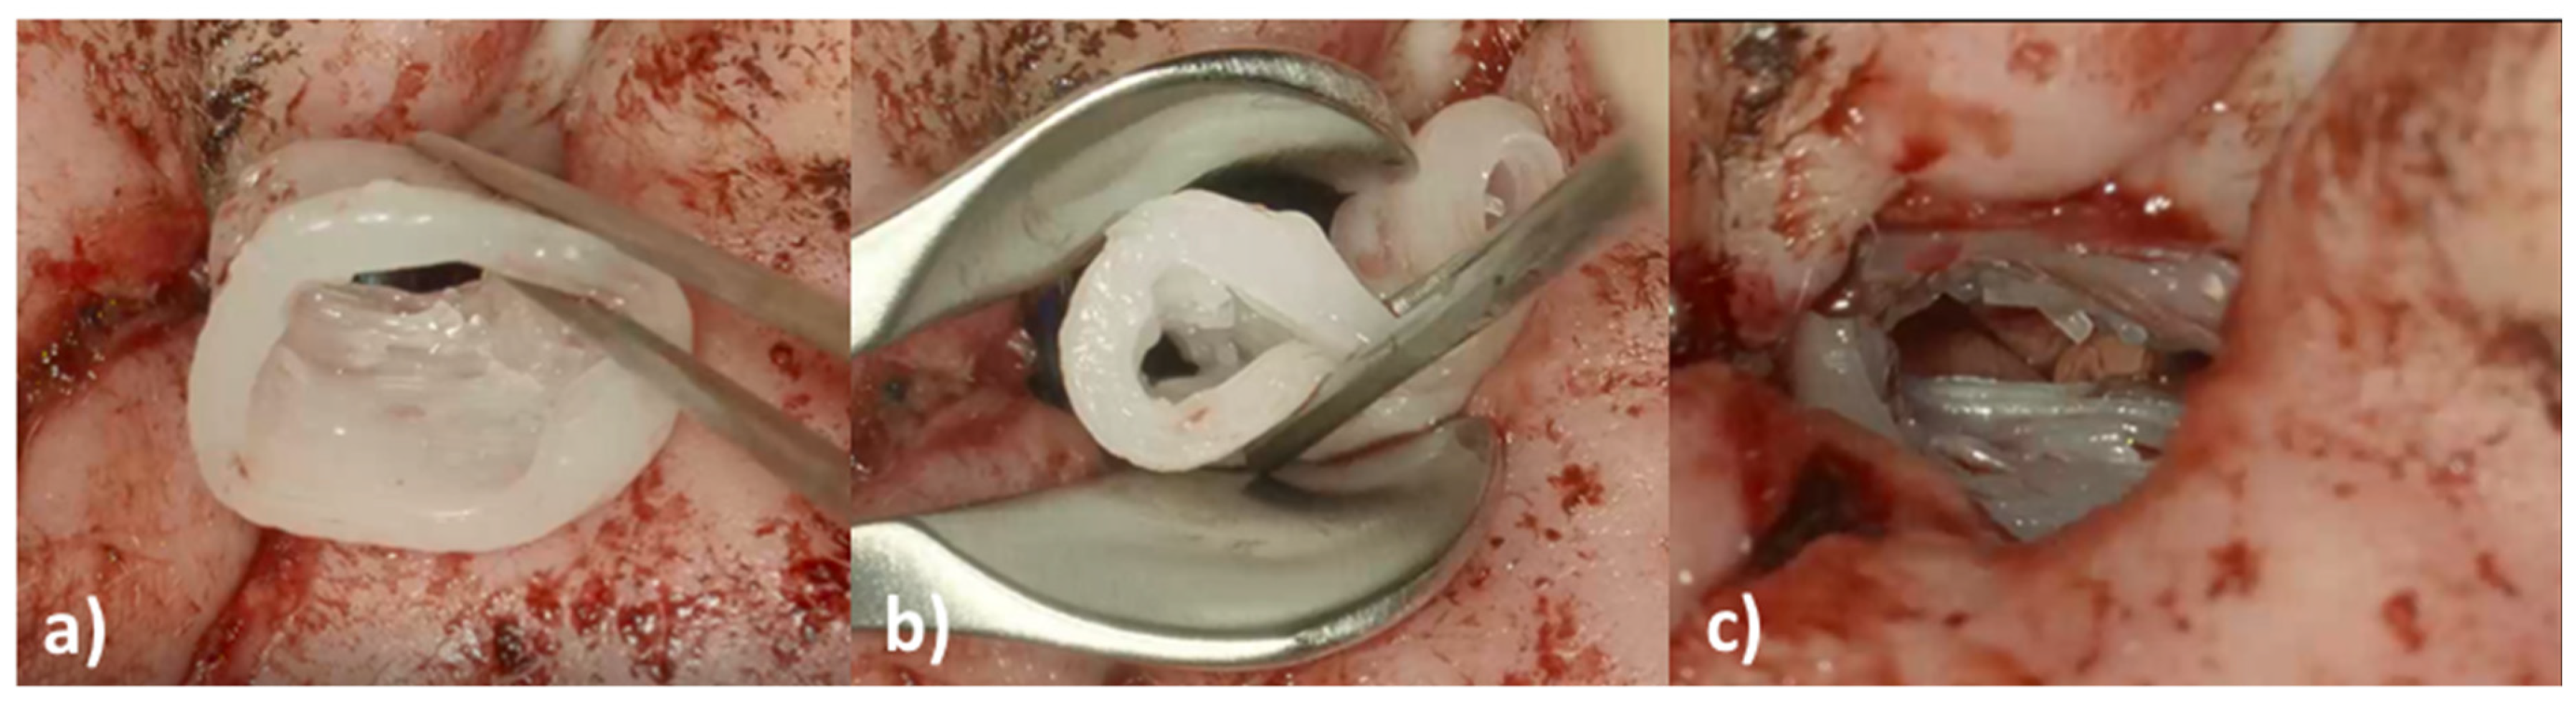

An eight-year-old girl with the diagnosis of unilateral congenital microtia and atresia of the EEC on the right side presented to our tertiary care hospital in January 2021. She had a patient history of multiple surgeries including reconstruction of the bony EEC and tympanoplasty type IIIa on the right in May 2018 and two revision canaloplasties with tympanic membrane (TM) reconstruction after restenosis of the EEC on the right side in January 2019 and September 2019. The clinical exam showed a partial restenosis of the surgically constructed EEC on the right side. A cone beam computed tomography imaging of the temporal bone (CBCT; xCAT, Xoran Technologies, Inc., Ann Arbor, MI, USA) (Figure 1) demonstrated a partial restenosis of the EEC on the right, but an aerated middle ear space, a middle ear partial ossicular replacement prosthesis (PORP), and an aberrant facial nerve course.

Prior to the preclinical testing, the patient presented to our outpatient clinic. CBCT imaging of the temporal bone was performed (Figure 1) to capture the anatomy of the region of interest (ROI). The acquired data were saved as image slices in the DICOM (digital imaging and communications in medicine) format and the ROI was segmented manually by a trained ENT surgeon using 3D SlicerTM version 4.11 (Surgical Planning Laboratory, Brigham and Women’s Hospital, Harvard Medical School, Boston, MA, USA) (http://www.slicer.org; accessed on 1 November 2021) to build a 3D reconstruction of the bony EEC. The segmentation resulted in the isolation of the ROI through a semi-automatic process based on region thresholding of the bony edges of the EEC (Figure 2a). After segmentation, the implant surface was processed by applying the surface smoothing effect with the dimensionless parameter of 0.5 in 3D SlicerTM. All reconstructions were transformed into a hollow object with a wall thickness of 1.5 mm and then the ends facing to the TM and the opening of the EEC were cut. Subsequently, a stereolithography (STL) file of the digital model was generated (Figure 2b).

Figure 1. Cone beam computed tomography imaging of the temporal bone of the patient. (a) Coronal view of the external ear canal with the white arrowhead pointing to the restenosis; an aerated middle ear space and a middle ear partial ossicular replacement prosthesis (black arrowhead); (b) axial view of the external ear canal with the partial restenosis (white arrowhead).